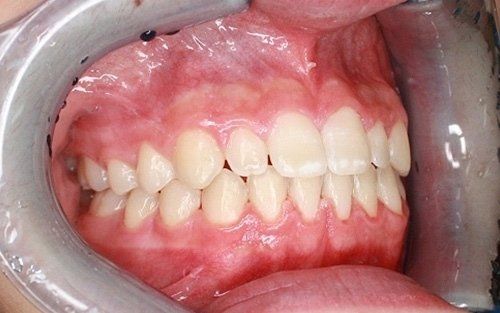

La "doppia fila" di denti: preoccupazione per i genitori

Una grande preoccupazione per i genitori è rappresentata dalla presenza contemporanea dei denti permanenti e dei denti da latte (che non cadono).Questa condizione non è affatto pericolosa per i denti permanenti, che prima o poi andranno a posizionarsi nella loro sede definitiva, dando l'ultima spinta ai dentini da latte, che cadranno definitivamente. Tranne rare accezioni, non vi è alcuna necessità di traumatizzare il bambino anticipando questo processo naturale con fastidiose estrazioni dentali.

Ecco un classico esempio di contemporaneità di denti da latte e denti permanenti. Questa situazione preoccupa sempre molto i genitori.